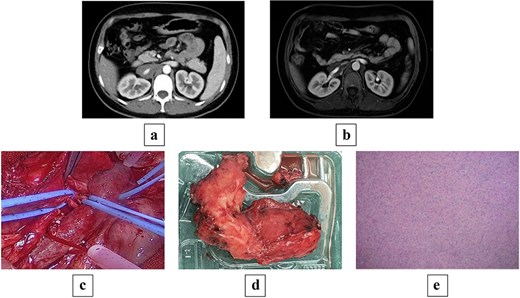

Contrast-enhanced computed tomography (CT) on admission showed an occupying lesion at the right renal hilum and adjacent to the IVC, with clear borders, uniformly low density, and heterogeneous progressive enhancement post-contrast, suggestive of a possible lymphangioma (Fig. 1a). Subsequent magnetic resonance imaging (MRI) with plain and contrast-enhanced sequences revealed a right retroperitoneal mass measuring ~24 × 36 × 68 mm. On T1WI, it appeared as a uniformly low signal; on T2WI, as heterogeneous high signal. Post-contrast, it showed clear borders with heterogeneous enhancement. The lesion encased the IVC and right renal vein in an "encasing" growth pattern, without evident vascular lumen invasion or stenosis, favoring GN or lymphangioma (Fig. 1b). Endocrine evaluation, including plasma renin activity, upright posture direct renin, and aldosterone levels, showed no significant abnormalities.

(a) Preoperative contrast-enhanced CT shows a mass-like soft tissue density shadow at the right renal hilum and adjacent to the IVC, with uniform density accompanied by punctate dense shadows at the posterior margin, measuring ~24 × 34 × 70 mm, encasing the IVC and right renal artery and vein, with partially unclear boundaries at the horizontal portion of the duodenum. (b) Preoperative MRI shows a mass-like soft tissue signal shadow at the right renal hilum and adjacent to the IVC; post-contrast scan reveals mild enhancement at the edges of the lesion, which encases the IVC and right renal artery and vein. (c) Intraoperative view of the tumor encasing the renal artery and IVC. (d) Gross pathology specimen of the resected irregular tissue fragment (8 × 6 × 2.5 cm) with gray–white cut surface, firm consistency, and attached portion of adrenal gland (2 × 1.5 × 0.3 cm). (e) Histopathological micrograph revealing mature ganglion cells with large, round nuclei and prominent nucleoli (hematoxylin and eosin stain; original magnification ×200).

Following multidisciplinary discussion (MDT), open abdominal exploration was performed. Intraoperatively, a mass was identified anterior to the IVC, encasing the IVC and right renal artery and vein, with adhesions to the vessels lacking a clear plane. The mass was firm, measuring ~5 × 8 × 10 cm. Retroperitoneal mass resection was conducted, with temporary occlusion of the bilateral renal arteries and veins (Fig. 1c). During dissection, the tumor portion had completely encased the renal vein wall, and no clear structural layer could be identified for dissection; the risk of forceful separation was high, prompting a shift to an ‘en bloc resection’ strategy, with minimal resection along the outer edge of the vein wall (~2–3 cm). Adherent portions to the renal vein were excised en bloc with the venous wall, followed by renal arteriovenous repair, resulting in blood loss of ~200 ml throughout the process.

Postoperative pathology: One irregular tissue fragment (retroperitoneal mass) measuring 8 × 6 × 2.5 cm, with gray–white cut surface and firm consistency, attached to a portion of adrenal gland measuring 2 × 1.5 × 0.3 cm (Fig. 1d). Immunohistochemistry: AE1/AE3(−), SOX10(+), S100(+), Ki67(<2%+), Melan A(−), Syn(+), CgA(+), PAX8(−), Inhibin(−). Mature ganglion cells were observed, scattered with large, round nuclei and prominent nucleoli, consistent with GN (Fig. 1e).